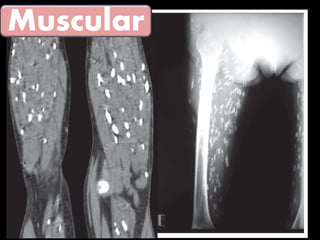

La cisticercosis y la teniasis son causadas por el mismo parásito, Taenia solium, pero deben tratarse por separado. La cisticercosis ocurre cuando los huevos del parásito se desarrollan en tejidos como el cerebro, los ojos y los músculos, mientras que la teniasis ocurre cuando el parásito adulto vive en el intestino delgado.